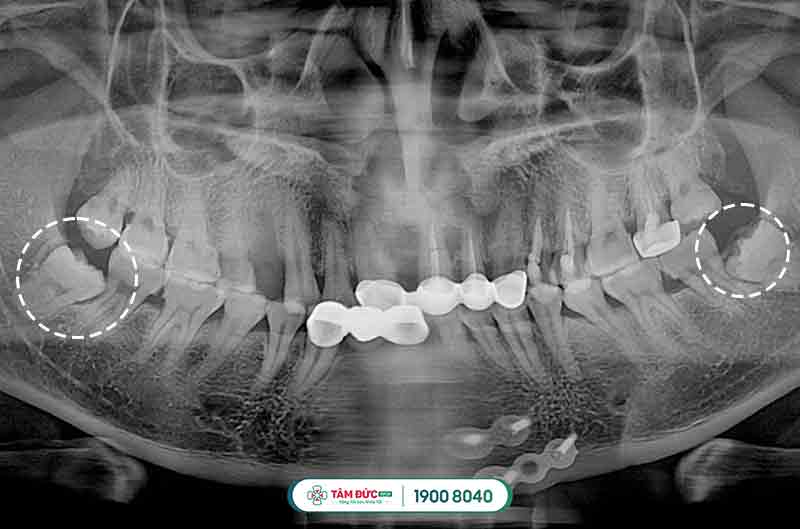

Đối với các trường hợp mọc răng khôn bị thiếu chỗ vì lúc này xương hàm đã ngừng tăng trưởng và phát triển, chịu tác động bởi quá trình ăn uống hàng ngày, khiến răng khôn bị mọc ngầm dưới nướu, mọc lệch đâm vào má, vào răng bên cạnh gây nên tình trạng đau răng khôn dữ dội, khó chịu và ảnh hưởng đến cấu trúc hàm mặt, sức khỏe răng miệng.

Răng khôn mọc lệch đâm vào răng kế cận

Răng khôn mọc ngầm thường có hiểu hiện làm nướu sưng tấy, viêm đỏ, khó há miệng. Vì xương hàm không có đủ vị trí nên nó sẽ đâm sang răng bên cạnh, nó sẽ làm chiếc răng khỏe mạnh kế bên dần bị tiêu hủy, lung lay có thể dẫn đến sâu, nặng hơn nó sẽ khiến chiếc răng này bị xô đẩy chèn ép và rụng đi gây mất răng. Răng khôn mọc lệch, ngầm thường gây ra những cơn đau răng khôn âm ỉ kéo dài trong khoản 2 tới 3 ngày.

Nhổ răng khôn không đau là một ca phẫu thuật nhỏ, không gây mê mà chỉ gây tê cục bộ tại vị trí cần nhổ giúp giảm cảm giác đau nhức cho cho chúng ta, được chỉ định cho những người có răng khôn mọc lệch, mọc ngầm, răng khôn bị tai biến, dính khớp…được thực hiện nhanh chóng dưới sự hỗ trợ của máy móc hiện đại và bác sĩ có chuyên môn cao.